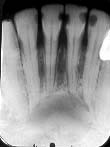

| Lesões do Periápice e Periodonto |

Lesões do Periápice e Periodonto